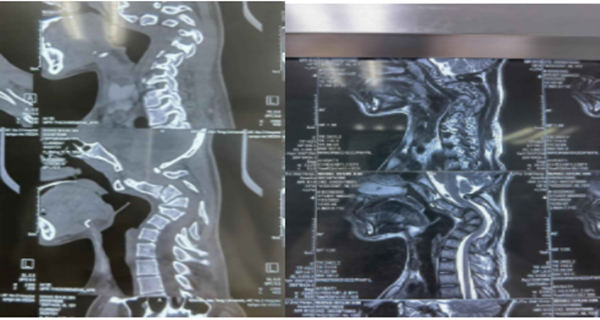

据文献报道,颈椎后凸≥30°即称为重度的颈椎后凸畸形,并且在颈椎过屈过伸时后凸角度改变小于50%称为僵硬性后凸畸形。而该患者,其后凸角度达到110°,且在过屈过伸位置上后凸角度几乎没有变化。对于这种严重且僵硬的颈椎后凸畸形,手术的目的不光是解决畸形的问题,同时还需完成脊髓的减压,给受损的脊髓神经根创造恢复的空间。然而手术的风险和困难也来源于此,在矫正僵硬颈椎畸形时,会在短时间内使颈椎以及脊髓的空间位置发生剧烈的改变,在这一过程中,如何避免原本脆弱的脊髓张力增加而导致四肢瘫痪,是一个严重而极富挑战性的难题。这么严重的畸形,国内外都没有成熟的治疗标准,国内也仅仅几家大医院开展过类似手术,而且只是零星的个案报道。李浩鹏主任医师团队结合这个患者特点,详细评估每张影像学资料,为患者制定了术前牵引,手术先前路松解,再后路截骨固定,再次前路固定的周详的治疗方案。